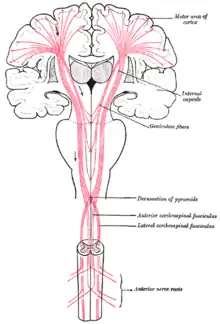

Le faisceau cortico-bulbaire (ancien faisceau cortico-nucléaire ou faisceau géniculé ou faisceau cortico-géniculé) est une portion de la voie pyramidale, formée d’axones de neurones moteurs centraux, qui innerve les noyaux moteurs des nerfs crâniens.

Le faisceau cortico-bulbaire relie le cortex moteur aux noyaux, origines des nerfs crâniens, dans le tronc cérébral. Dans son chemin, il traverse le genou de la capsule interne, ce qui lui vaut le qualificatif de « géniculé ».

En fait, le faisceau cortico-bulbaire comporte deux contingents de fibres :

- le contingent oculo-céphalogyre qui se termine dans les noyaux des nerfs oculomoteur (III), trochléaire (IV), abducens (VI) et accessoire (XIm) ;

- le reste des fibres se terminent dans les noyaux moteurs des nerfs d'origine branchiale trijumeau (V), nerf facial (VII) , ambigu (IX, X, XIb) et le noyau du nerf hypoglosse (XII).

Il descend dans le tiers interne du mésencéphale et abandonne ses fibres aux noyaux moteurs des nerfs crâniens. Il distribue ses fibres de manière bilatérale pour l'ensemble des nerfs crâniens à l'exception du noyau du nerf VII inférieur pour lequel les fibres sont distribuées de manière controlatérale seulement[1]. Ce qui explique qu'une lésion centrale (cortex) unilatérale s'exprime cliniquement en cas d'atteinte du VII inférieur par une faiblesse des muscles de la partie inférieure du visage (sous les yeux) controlatérale à la lésion. Par exemple, une atteinte de la partie moteur du cortex frontal gauche entraîne l'affaissement de la commissure labiale droite.